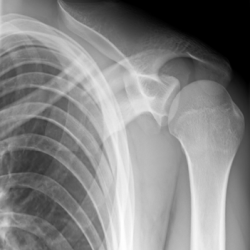

Röntgenbilder